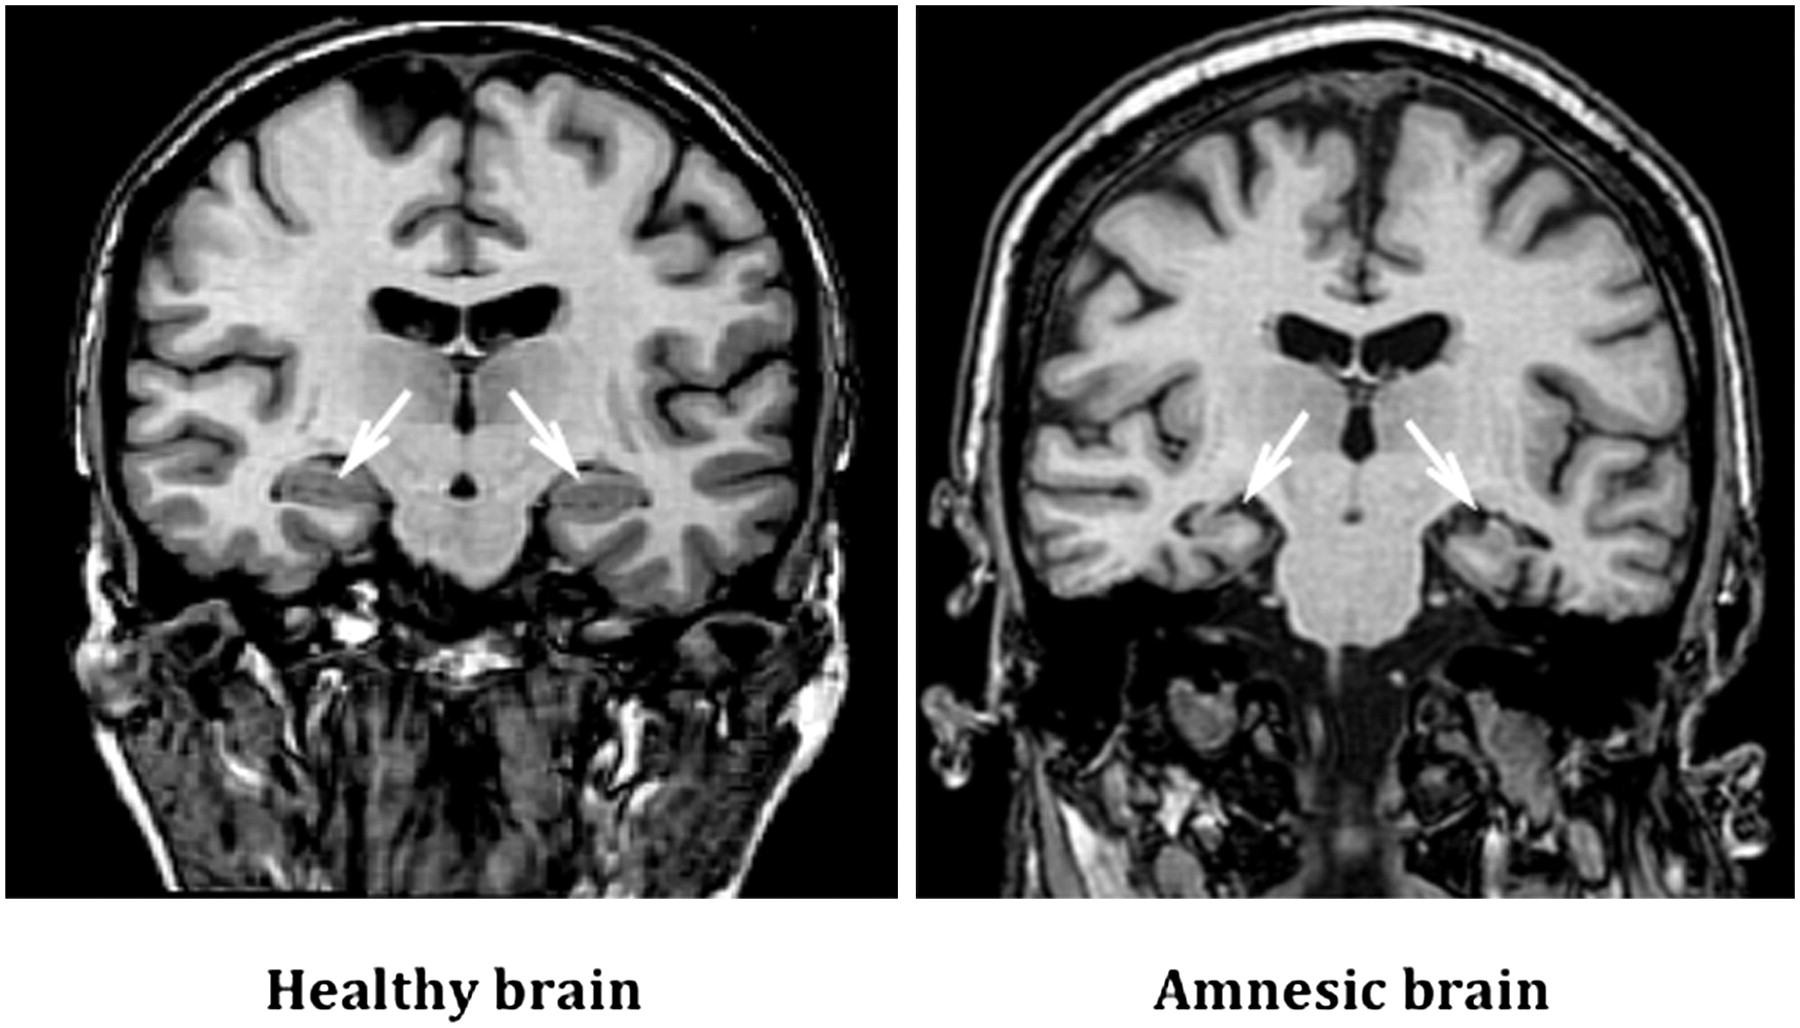

Психогенная амнезия